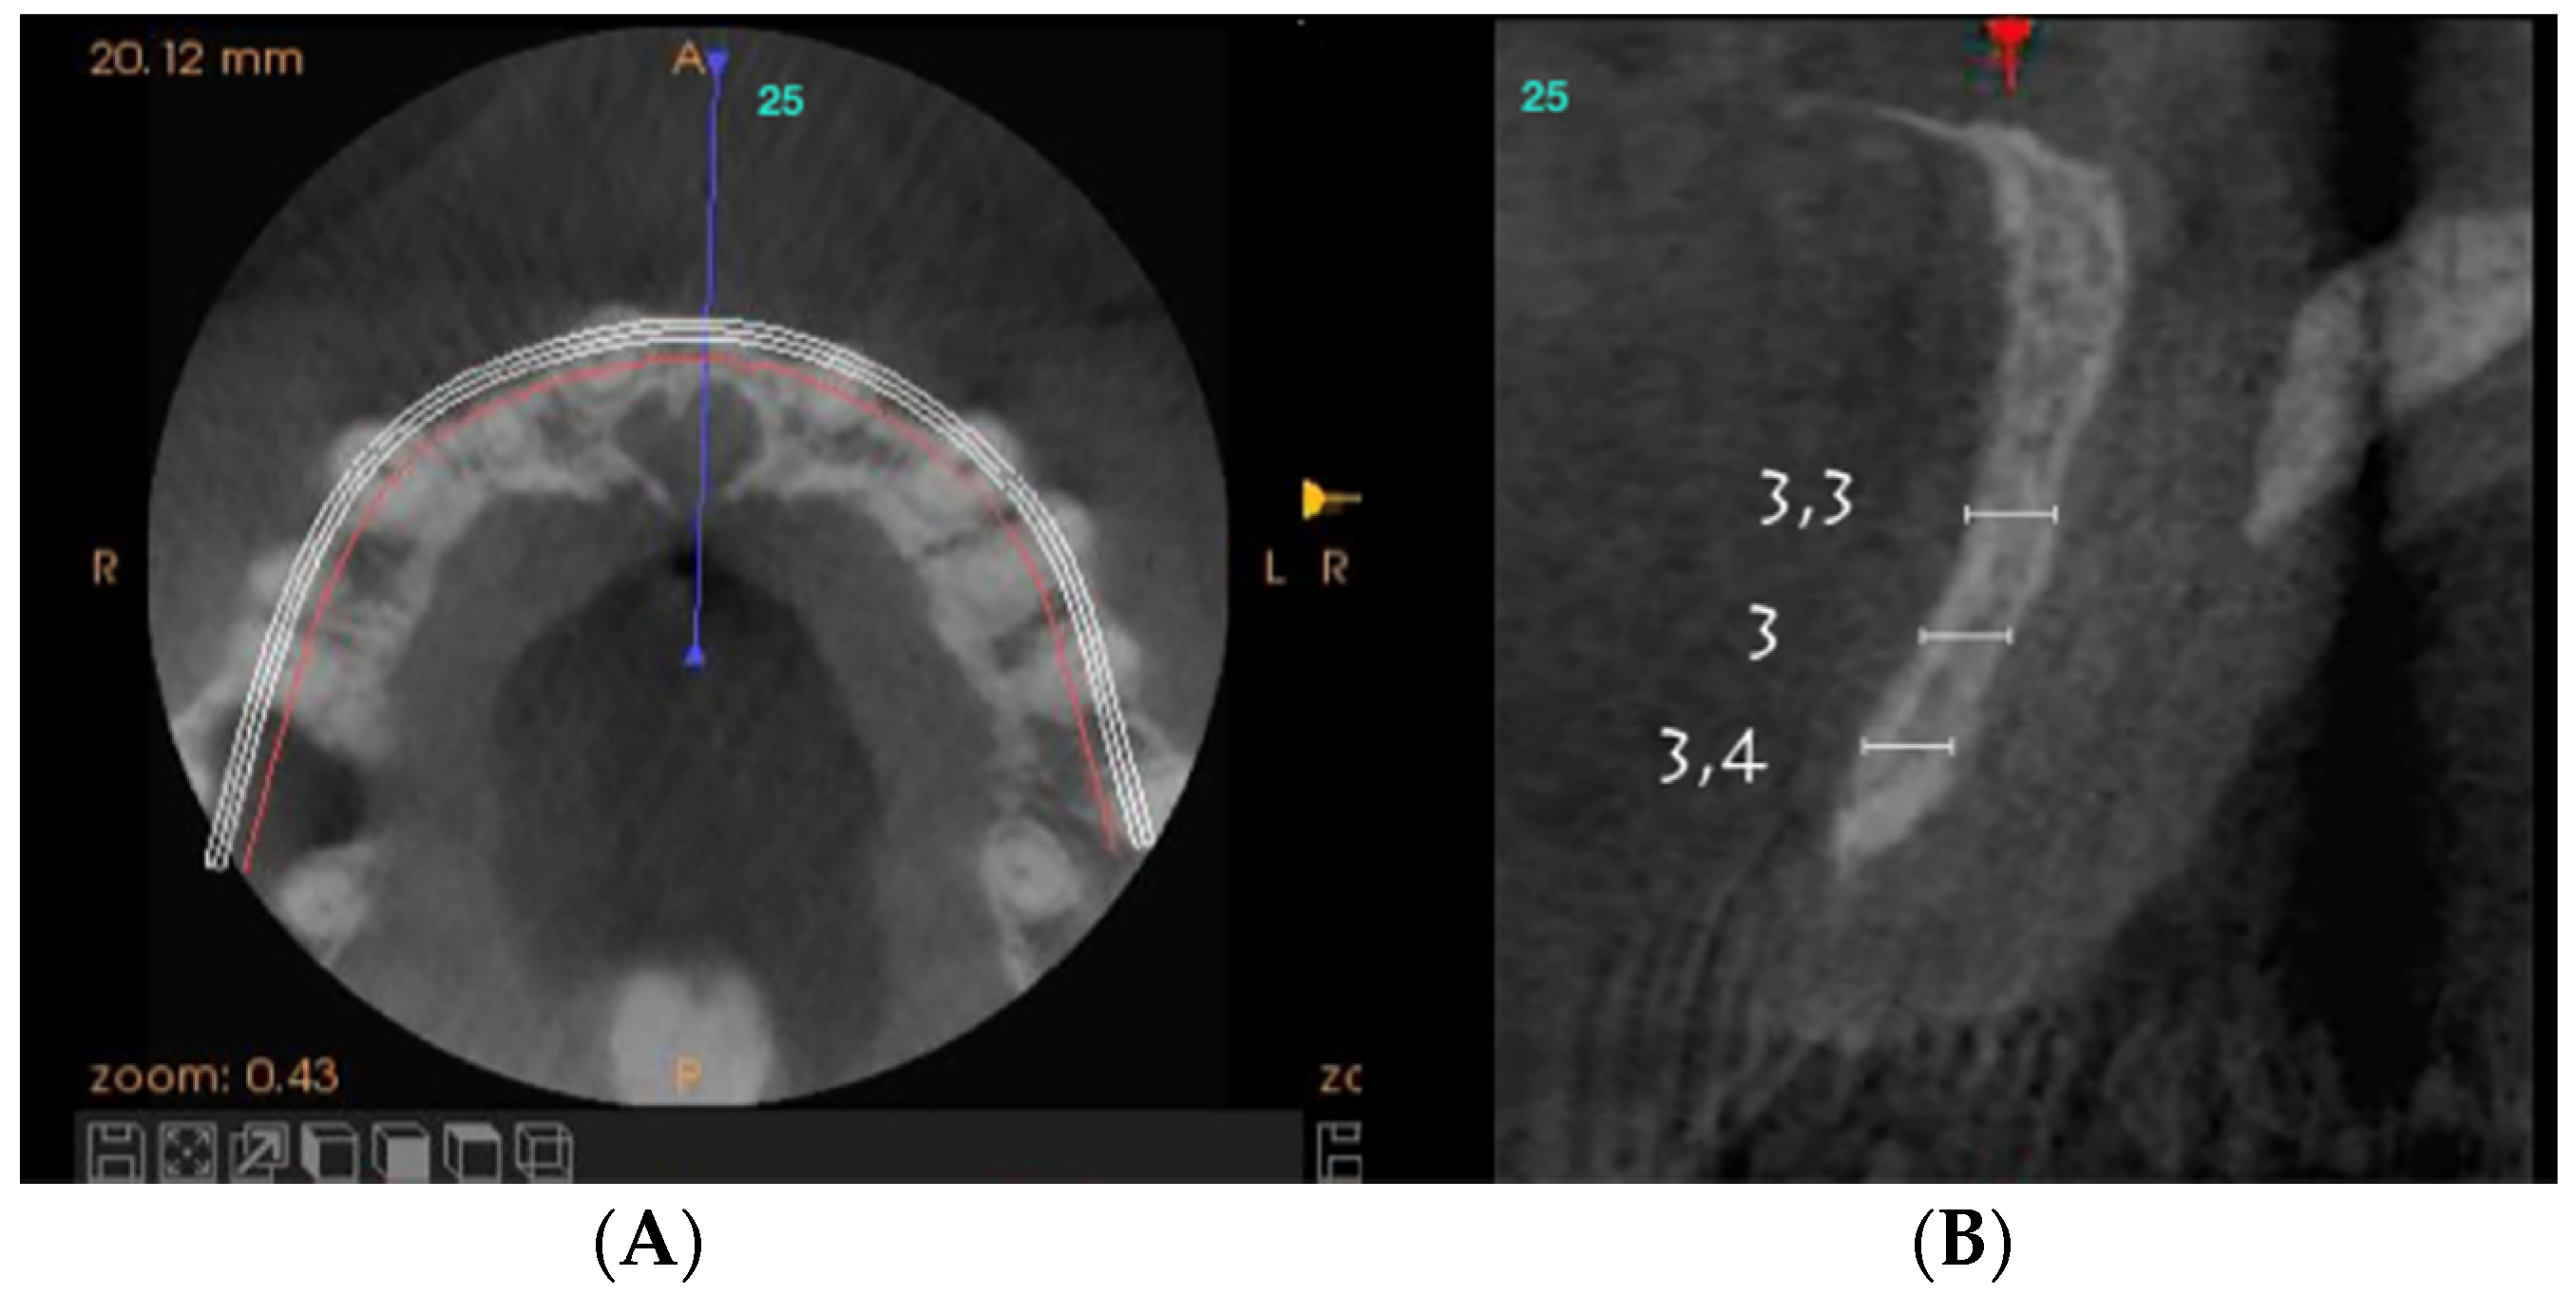

Axial sections corresponding to the middle part of the NPC showed the collapse of the vestibular plate and revealed the conduit’s size. All the cases presented thinning of the palatal ridge due to marked widening of the incisive foramen (Figure 2); so, according to the SAC Classification (i.e., simple, advanced, or complex), they were categorized as complex [2]. In addition, careful consideration had to be given to the nasopalatine bundle for correct three-dimensional positioning of the implant. Since the vertical and horizontal defects demanded bone augmentation before implant placement [17], a diagnostic wax-up was performed to determine the amount of bone needed in each case.

Figure 2.

Representative sections of a Cone Beam Computed Tomography (CBCT) scan in which the bone thickness of the maxillofacial region and the widening of the incisive foramen are observed. (A) Occlusal view. (B) Sagittal view.